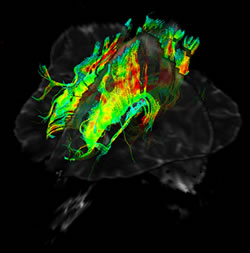

千葉大学医学部附属病院放射線科のMRI導入の歴史は古く、1980年に千葉MR研究会が発足し、翌1981年に当科第2代教授有水昇先生を中心に第1回日本磁気共鳴医学会が開催されています。MRI画像は組織分解能が高いことが特徴であり、腫瘍の性状を詳しく分析することが可能です。脳疾患の診断にも欠かせない診断装置です。欠点としてはCTに比べて検査時間が長く、また検査中に大きな音がすることが挙げられますが、CTのようにX線を使いませんので被曝はありません。

このように多くの日常診療の画像を撮っていますが、研究のための画像検査も行っています。例えば、従来の撮像法では評価の難しかった腱や靭帯、神経といった微細な構造物を視覚化できる撮像法は、各科の医師からも診断に役に立つとのご評価を頂いています。